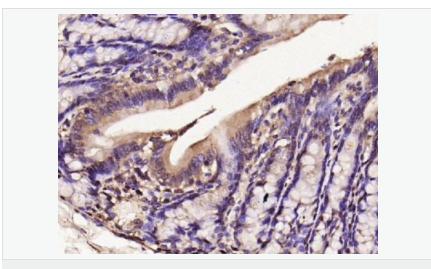

產品應用WB=1:500-2000 IHC-P=1:100-500 IHC-F=1:100-500 Flow-Cyt=1μg/Test ICC=1:100-500 IF=1:100-500 (石蠟切片需做抗原修復)

image.png